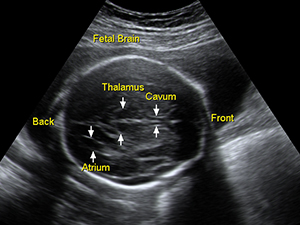

Fetal brain in the second trimester